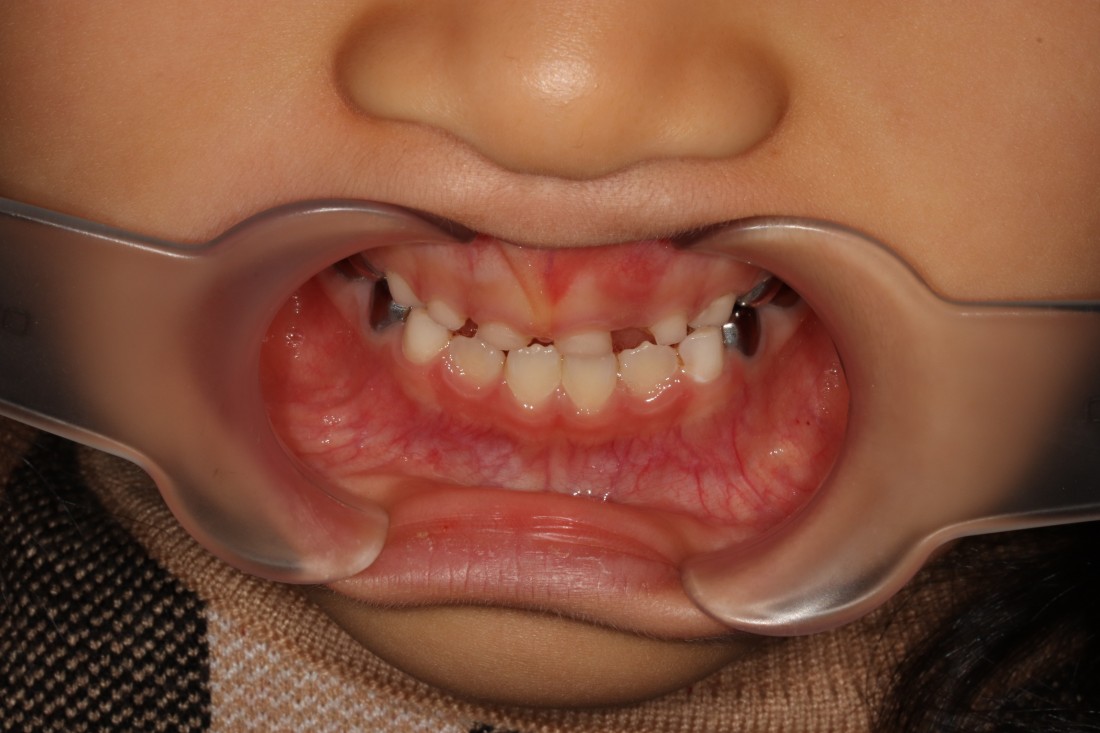

광주 부정교합 치과에서는

프리올소 교정장치를 이용하여

반대교합을 개선하고 있습니다.

프리올소 교정장치는

일본의 교정전문의가 개발한

뺐다 꼈다 할 수 있는

탈착식 교정장치를 말하는데요.

페이스마스크, 프랑켈 등의

부정교합 개선 장치에 비하여

부피감이 작고 착용시간이 짧은 편이라

아이들이 빨리 적응할 수 있습니다.